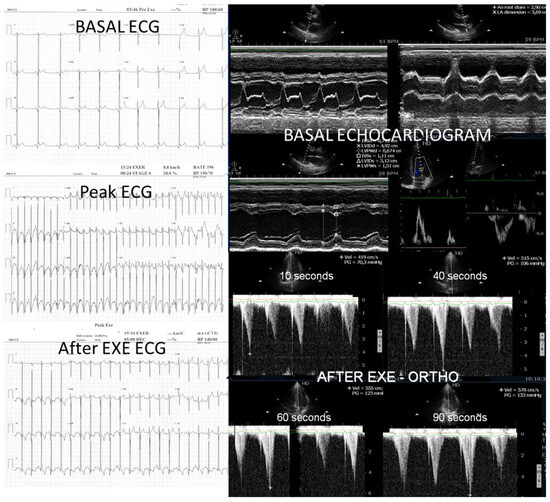

We observed the development of intraventricular pressure gradients (IVPGs) in adolescents without left ventricular hypertrophy upon assumption of an upright posture prior to exercise—a phenomenon previously described in patients with hypertrophic cardiomyopathy [3]. At the onset of exercise (Figure 5), the IVPG initially decreased, likely due to increased preload resulting from activation of the lower limb musculature. However, as exercise progressed, the IVPG steadily increased (Figure 6). After exercise, maintaining an upright posture led to a more pronounced reduction in preload, compared to a supine position. This hemodynamic shift likely accounts for the post-exercise elevation in IVPG observed in most adolescents studied. This postural response may also explain the orthostatic recovery IVPG observed in one highly symptomatic adolescent who presented with exertional angina and ST-segment abnormalities (Figure 7). Additionally, Figure 8 illustrates the impact of beta-blocker therapy on ESE findings in one patient, including the titration of atenolol to a dose of 50 mg, underscoring the clinical relevance of individualized treatment.

Figure 8.

This composite image shows results obtained from an adolescent in the study during three exercise stress echocardiograms (ESE): the first shows significant IVPG; the second shows IVPG, despite 2.5 mg of bisoprolol having been taken; and the third shows nonsignificant IVPG, with 5 mg of bisoprolol having been taken.